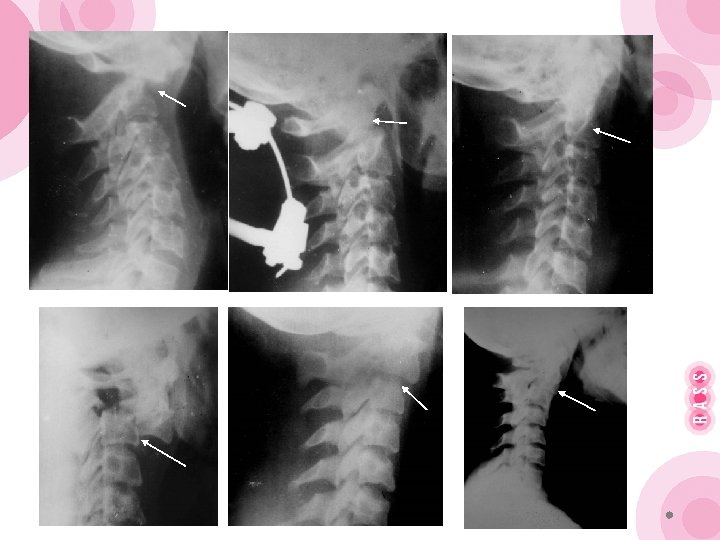

Гало-аппарат стал массово использоваться при переломах Джефферсона, переломах зубовидного отростка С 2, переломах «палача» , а также после стабилизирующих оперативных вмешательств, особенно когда выполняется обширная резекция позвонков (опухоли, инфекционные поражения, анкилозирующий спондилоартрит). Противопоказанием к наложению галоаппарата является нестабильные переломы костей черепа, повреждение кожных покровов головы в месте введения стержней.